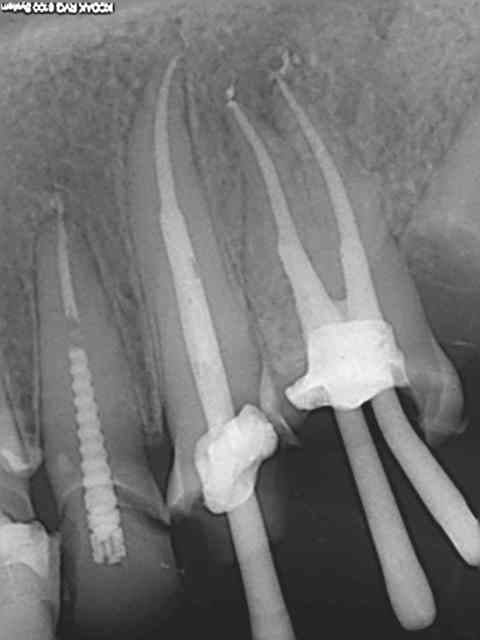

Tu fais comment ton obturation ? Lentulo pâte et monocone ?

Pas de lentulo. Scellement monocone ah+. Effectivement c'est le seul moment ou sur une dent mandibulaire la salive peut faire chier car j'enlève le lingua-fix pour la radio (optragate toujours en place).

D'un autre coté comme le résultat est reproductible il est rare de retirer les cones et de réinstrumenter.